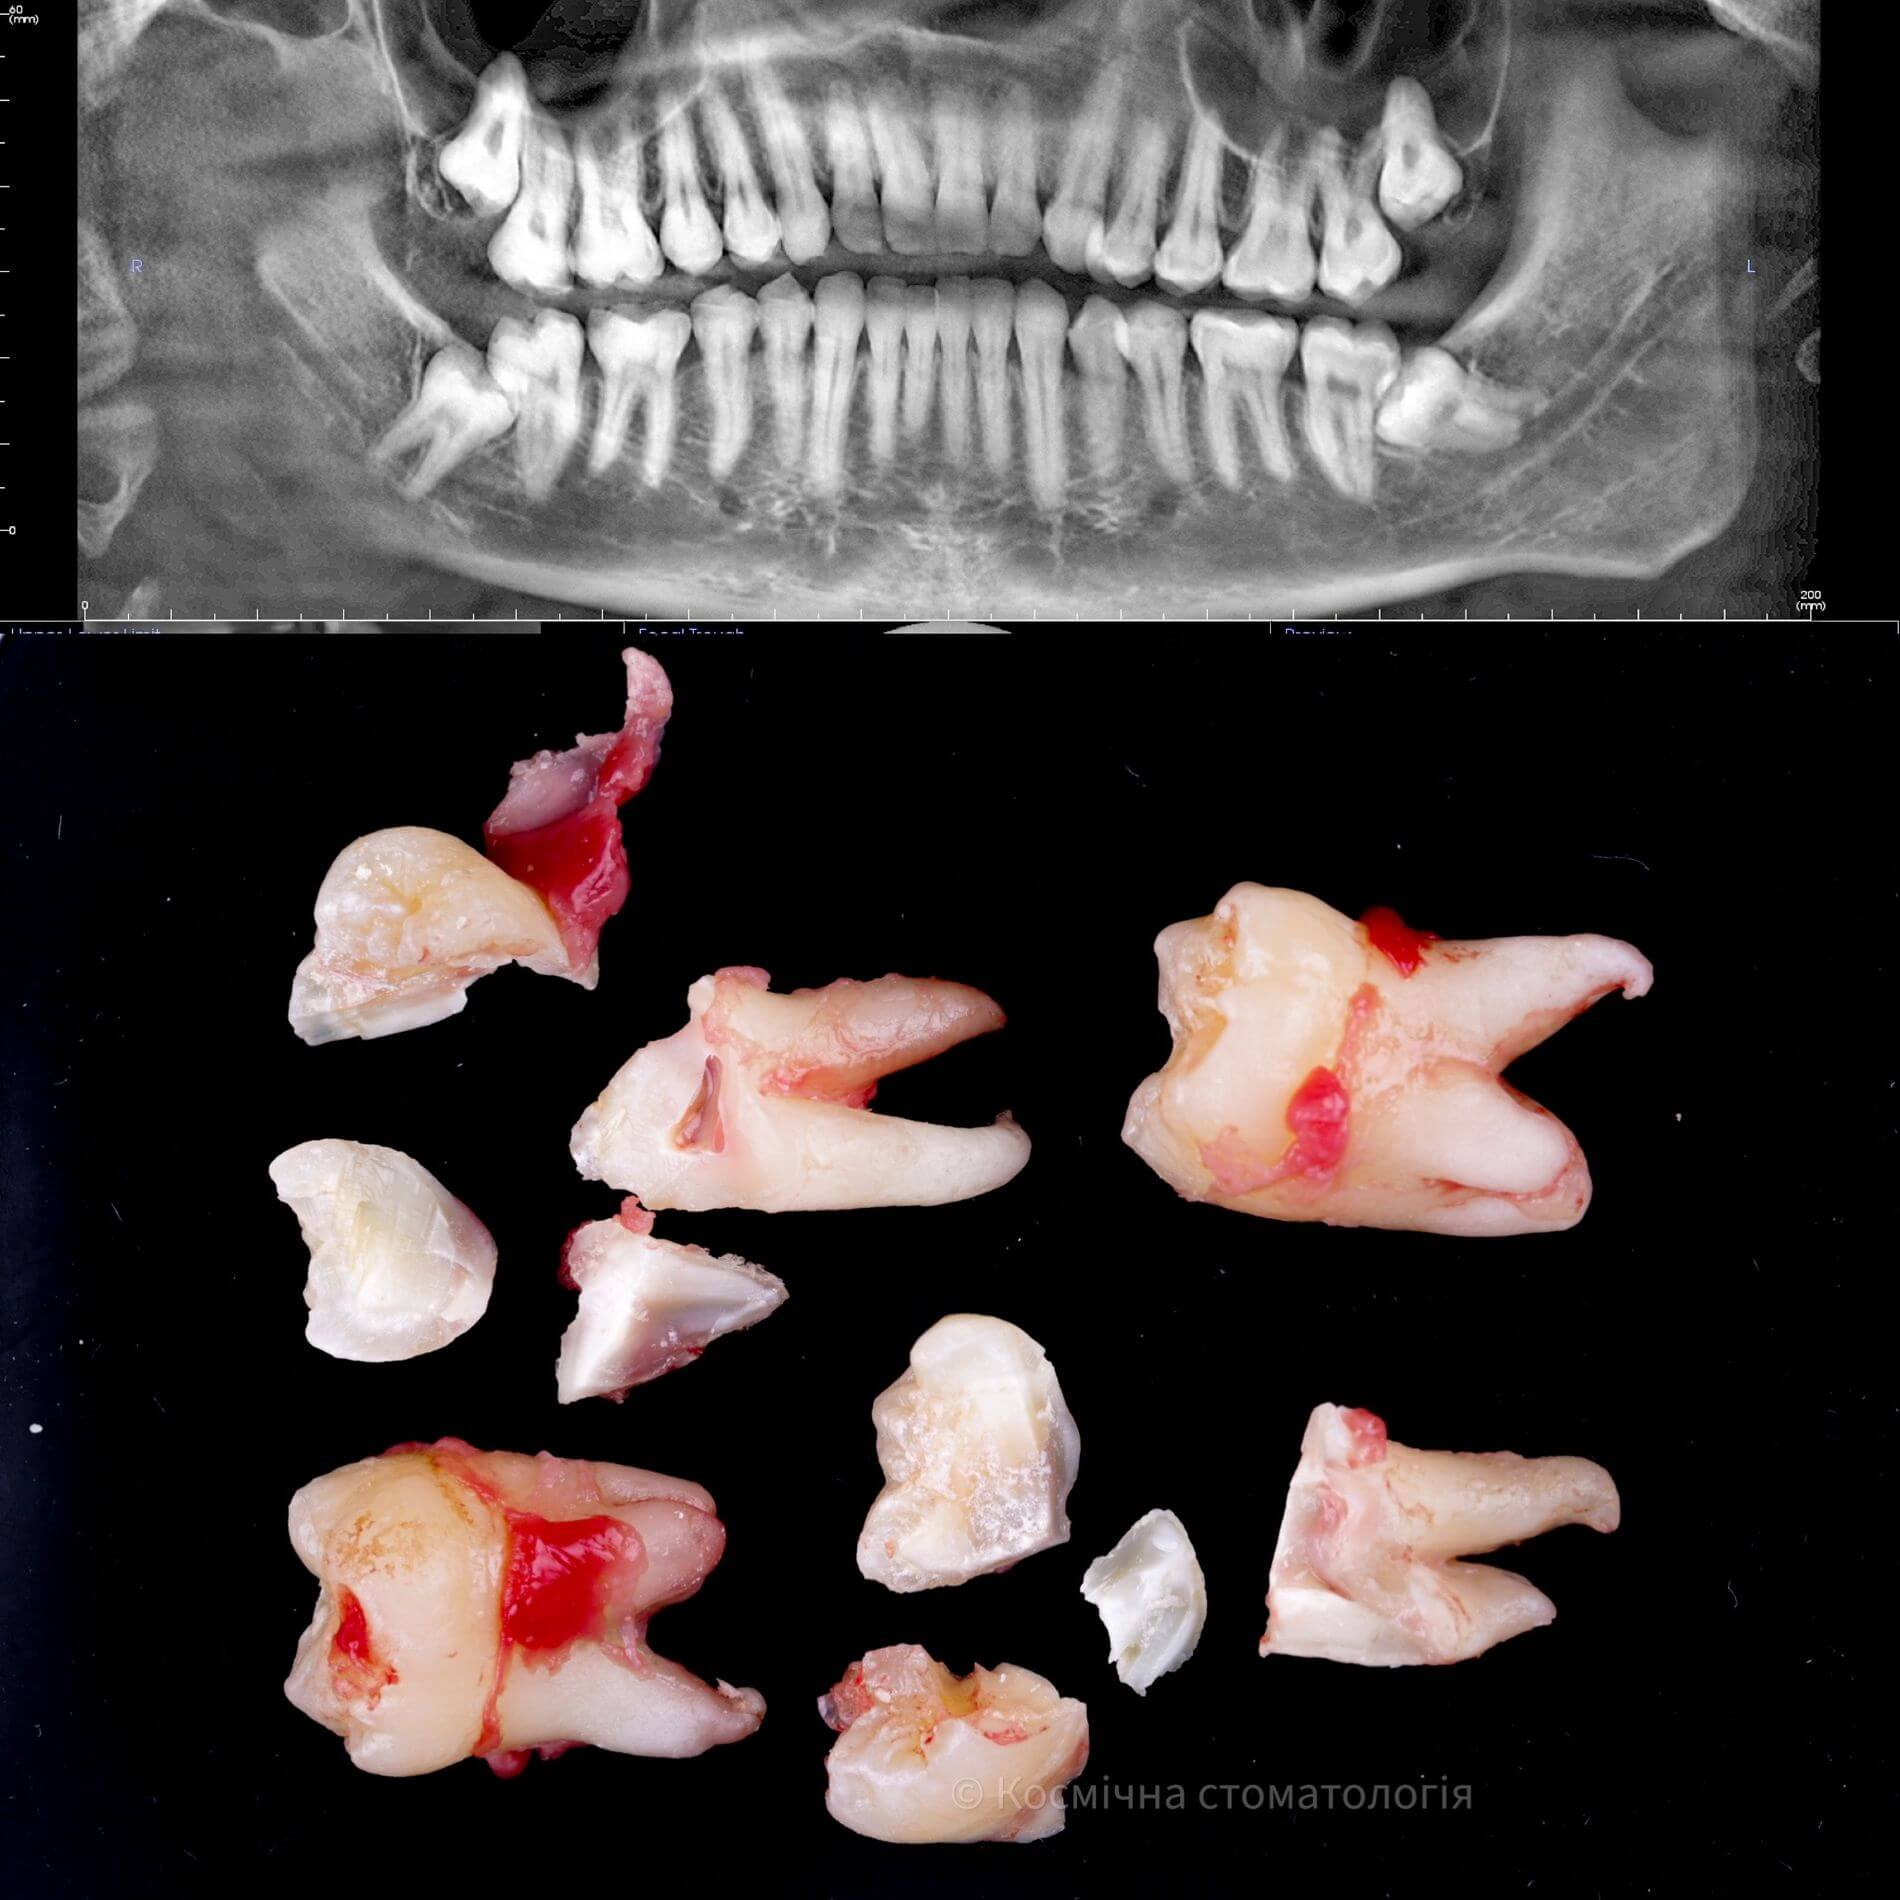

Галерея